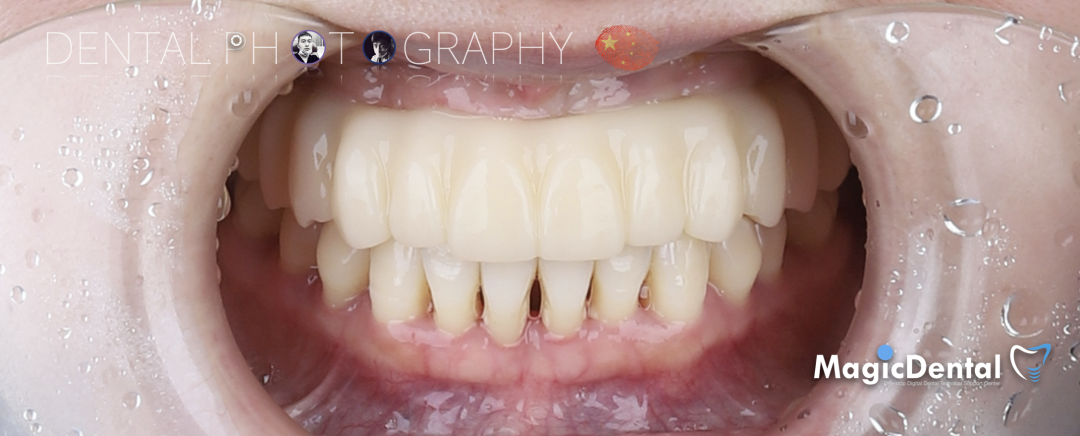

最终修复体制作完成

最终修复戴入口内后两周复查

术前术后对比